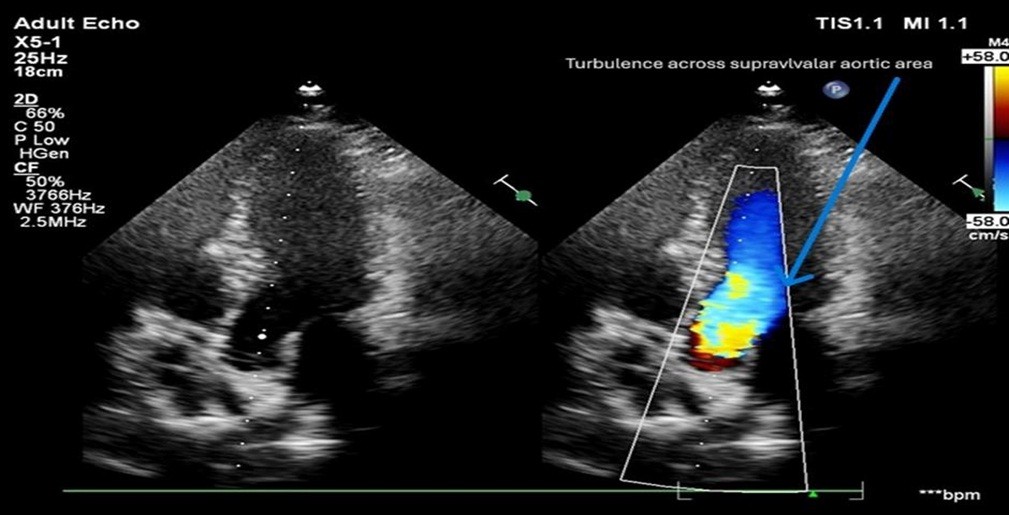

Cardiovascular imaging (echocardiography and cardiac magnetic resonce imaging, cMRI) confirmed SVAS. Transthoracic echocardiography revealed situs solitus, levocardia, supravalvular aortic gradient 44 mmHg, and mild concentric left ventricular hypertrophy (Fig. 3, 4).

Figure 3. Transthoracic echocardiography demonstrating supravalvular aortic turbulence.

Apical five-chamber view showing left ventricular outflow tract and ascending aorta (left), and color Doppler imaging (right) demonstrating mosaic turbulent flow across the supravalvular aortic region (arrow), consistent with flow acceleration at the level of supravalvular aortic narrowing.